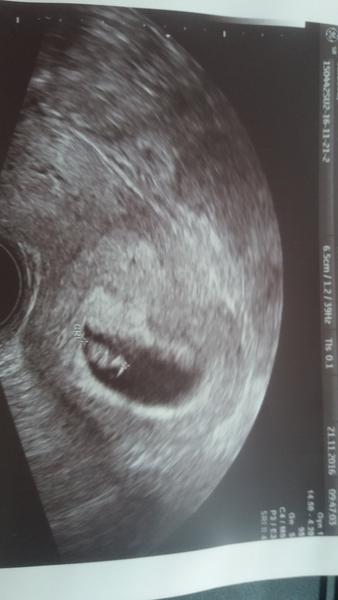

Ahoj holky tak u mě už to konečně pokročilo. V pátek oplodněno 10vajicek a v pondělí mám volat na embryologii kolik jich zůstává. A úterý nebo ve středu vychází transfer.☺👏